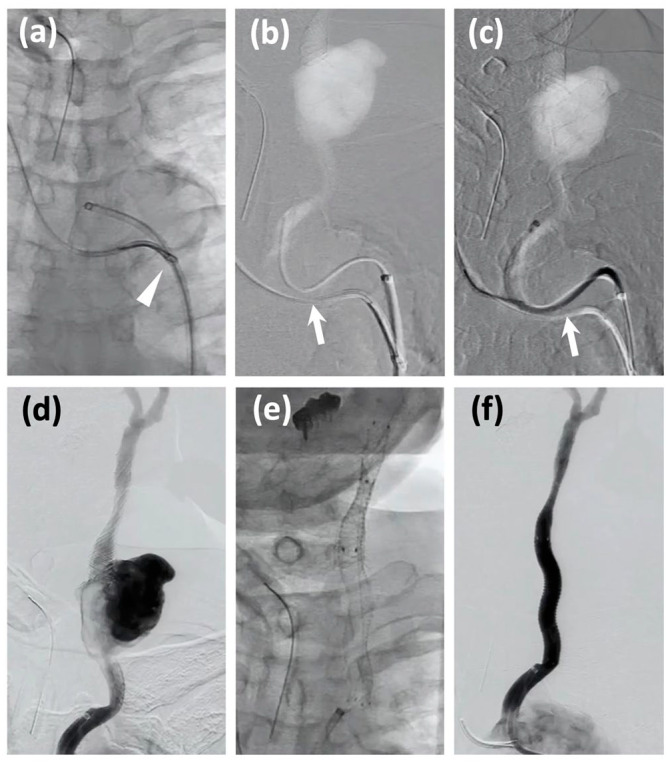

颈动脉爆裂综合征(CBS)是一种潜在的致命疾病,需要及时诊断和干预。CBS主要影响有头颈部恶性肿瘤手术或放疗史的患者。在本报告中,我们描述了一例CBS病例,该患者颈动脉支架植入术2个月后颈动脉破裂,既往有咽癌手术和放疗史。虽然颈总动脉口与破裂部位之间的距离很短,但“无接触”技术-在引导导管导航期间使用牛顿形硬内导管(Newton-T®,Medikit) -和圈套固定使手术稳定。两个自膨胀覆盖支架(GORE®VIABAHN®,GORE)覆盖破裂部位。尽管条件不利,但这些技术的结合导致了对即将发生的CBS(一种潜在的致命疾病)的有效管理。本病例报告强调了覆盖支架治疗CBS的可行性,以及在整个手术过程中用于引导导管导航和稳定的技术。

Carotid blowout syndrome (CBS) is a potentially fatal condition requiring prompt diagnosis and intervention. CBS primarily affects patients with a history of surgery or irradiation for head and neck malignancies. In this report, we describe a case of CBS in which the carotid artery ruptured 2 months after carotid artery stenting in a patient with a previous history of surgery and irradiation for pharyngeal cancer. Although the distance between the orifice of the common carotid artery and the ruptured site was short, the "no-touch" technique-using the Newton-shaped stiff inner catheter (Newton-T®, Medikit) during the guiding catheter navigation-and snare fixation enabled a stable procedure. Two self-expanding covered stents (GORE® VIABAHN®, Gore) covered the ruptured site. Despite adverse conditions, the combination of these techniques led to effective management of impending CBS, a potentially fatal disease. This case report highlights the feasibility of covered stents for CBS and the techniques used for guiding catheter navigation and stabilization throughout the procedure.